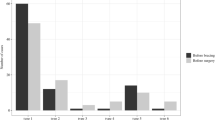

Significant kyphotic deformations with Cobb angles of about 45° (p < 0.01) were created in five rabbits, and no complications occurred throughout the experiment. The rabbits are still very much alive and do not show any signs of discomfort.